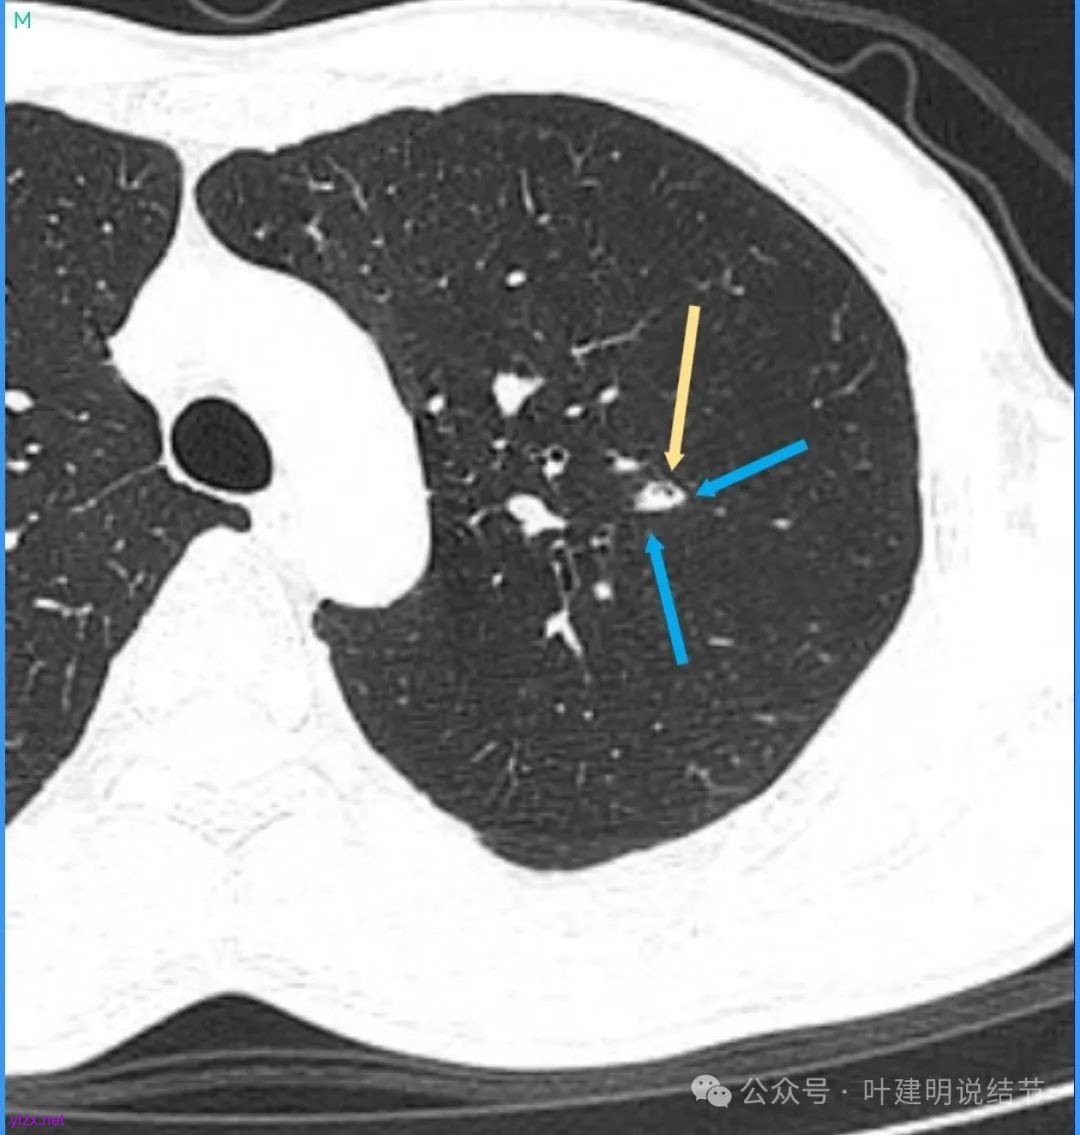

再看看近半年前2024年11月时的影像:

我们发现一是病灶与25年3月的几乎没有区别,二是原来蓝色箭头处不太像血管,而是结节边缘的一部分,而结节灶内又是有扩张支气管的。